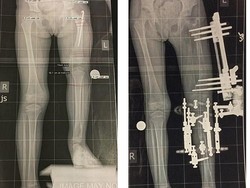

Menjadi orang tua dari anak penyandang rare disorder memiliki cerita tersendiri. Lalu, apa jadinya ketika para orang tua berkumpul dan berbagi cerita?